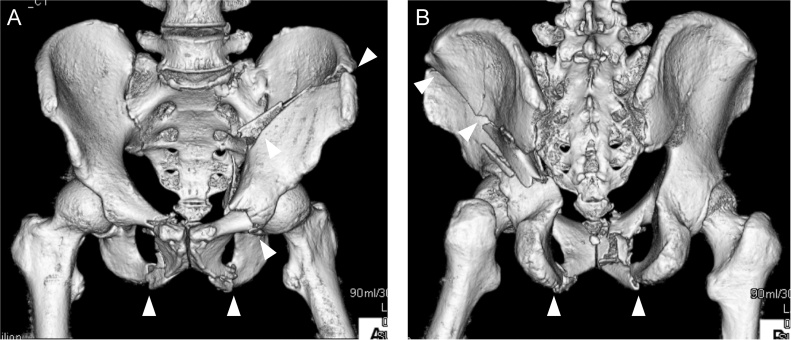

A 59-year-old man was hit by a car and brought to our emergency department. His Glasgow Coma Scale score was 6 (E1V1M4) and blood pressure was low. Radiographs and computed tomography (CT) showed a both-column fracture in the left acetabulum and bilateral pubic bone fractures (Fig. 1A,B). Brain CT initially showed no signs of brain injury. We diagnosed hemorrhagic shock following the pelvic fractures and immediately performed transcatheter arterial embolization. He had accompanying injuries including an incomplete fracture of the C2 lamina, a right clavicle fracture, right rib fractures from the second to eighth ribs, and fractures of the left thumb and index finger, all of which were treated conservatively. Six days after the injury, we performed open reduction and internal fixation (ORIF) for the acetabular fracture using a low-profile pelvic plate system (DePuy Synthes Trauma, West Chester, PA, USA) through an ilioinguinal and Kocher–Langenbeck combined approach. He remained unconscious for 3 weeks, and a second brain CT scan showed a chronic subdural hematoma. He was transferred to a rehabilitation unit 1.5 months after the operation, still with a consciousness disorder.

Fig. 1.

CT image of the pelvis after injury, showing the both-column fracture in the left acetabulum and bilateral pubic bone fractures (arrowheads).

The patient unexpectedly presented to our hospital 6 months after the transfer. He could walk on his own and was completely conscious and alert, but he complained of discomfort in his left hip and difficulty in its motion. Physical examination revealed that his left hip joint was completely ankylosed with a range of motion 45° in flexion, 10° in abduction, and 20° in external rotation. Radiographs and CT revealed HO (Brooker class 4) [3] around the left hip joint (Fig. 2A,B). A bone scan showed intense uptake around the left hip (Fig. 3).

Fig. 2.

(A) Anteroposterior and (B) lateral pelvic radiographs before HO resection. HO (white dotted line) bridged the left hip posteriorly.